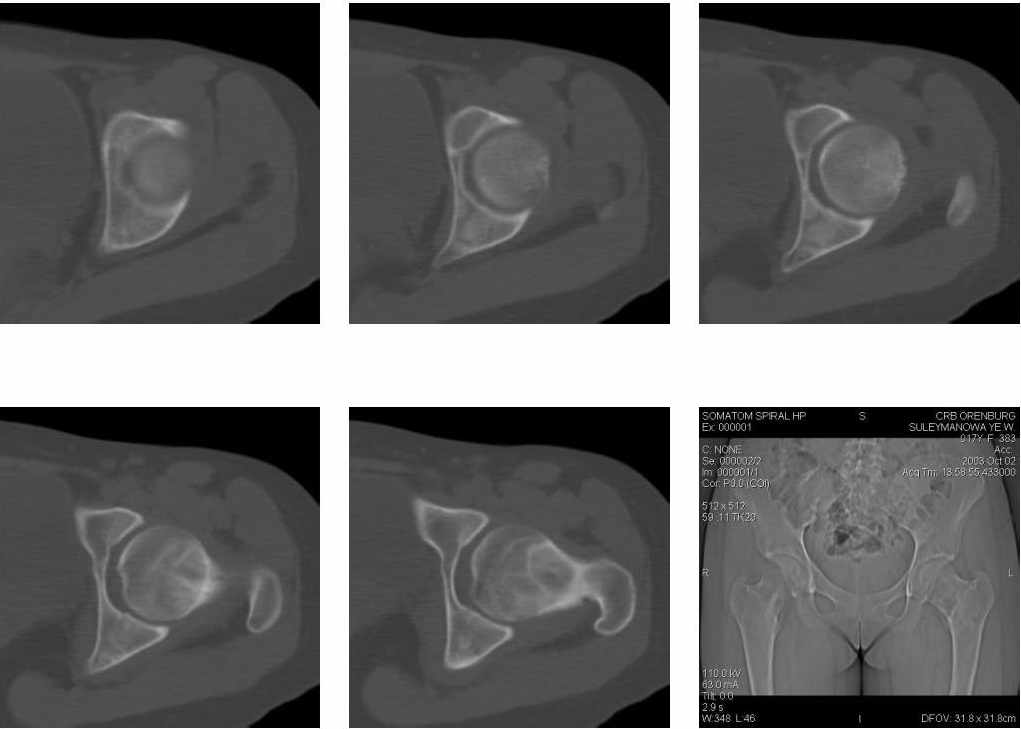

Молодая женщина 18 лет, последние 3 года стали беспокоить боли в левом тазобедренном суставе.

На рентгенограмме, утолщена шейка бедра и в шейке участок просветления. При КТ шейка утолщена на 9мм, в шейке полость24х21мм, стенки полости неровные и нечеткие, за пределы коркового слоя полость не выходит. Плотность содержимого полости 43 ед.Н. Предположительно должна быть солитарная киста шейки бедра, но смущает неровность и нечеткость контуров стенок. Ваше мнение господа? Какой предложите доступ для биопсии. Приложена первая серия снимков.